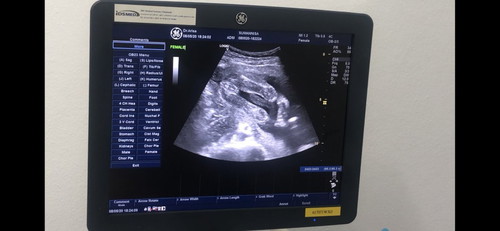

แม่ๆ ดูออกกันมั้ยเอ่ยว่าหนูผู้ชายหรือผู้หญิง ตอนซาวน์เพศหนูให้ความร่วมมือดีมากจ้าา แต่หลังจากนั้นทั้งพ่อทั้งแม่ทั้งหมอพากันหัวเราะเลยค่ะ ตัวเล็กซนไม่หยุดเลย 55555

เหมือนจะเป็นผู้หญิงเลยแม่